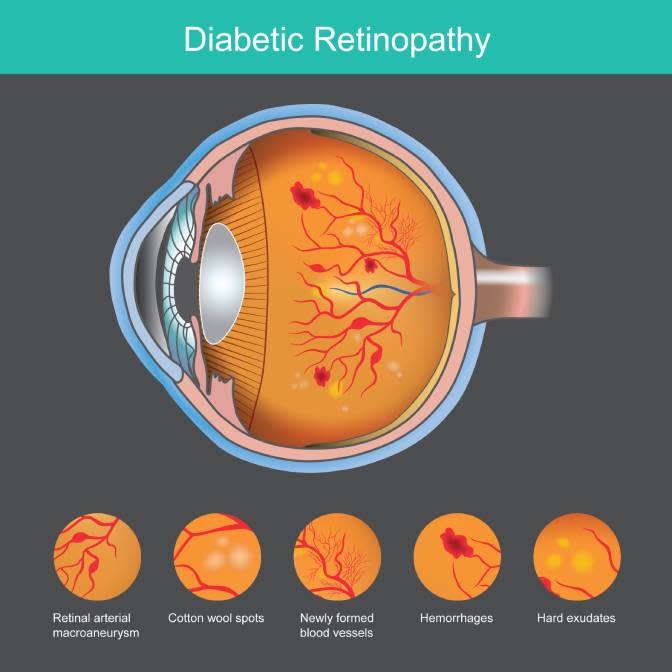

Vitrectomy is done for conditions like diabetic retinopathy, vitreous hemorrhage, vein occlusions, retinal detachment and macular hole. Small ports or openings are made in the coats of the eyeball, and fine instruments are introduced into the vitreous cavity which cut the vitreous and shave it off from the retina. Some cases require injection of gas or silicone oil, in which case a post-operative position is given to the patient.

The injections are administered to reduce the VEGF in the vitreous cavity which is responsible for various retinal diseases. Retinal diseases treated with these injections are diabetic retinopathy, macular edema, vein occlusions, macular degeneration, polypoidal choroidal vasculopathy and vitreous hemorrhage.

In diabetic retinopathy pan retinal photocoagulation is done. This involves treating the entire avascular retina with laser. While many hospitals do this in 3 separate settings, our advanced technology has allowed this to be completed in a single sitting in most patients. Laser helps to divert blood flow to the healthy retina while treating the unhealthy retina. This is required for advanced cases of diabetic retinopathy and vein occlusions involving retinal avascularity. If not done in time, the new vessels growing on the retina can bleed causing vitreous hemorrhage.

Diabetic Retinopathy Screening

Comprehensive retinal screening for diabetic patients to detect and prevent potential vision loss through early intervention.